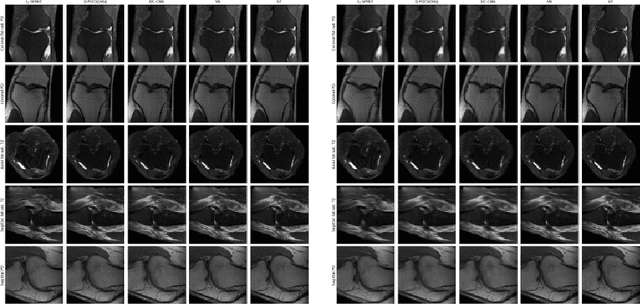

Abstract:Dynamic fetal heart magnetic resonance imaging (MRI) presents unique challenges due to the fast heart rate of the fetus compared to adult subjects and uncontrolled fetal motion. This requires high temporal and spatial resolutions over a large field of view, in order to encompass surrounding maternal anatomy. In this work, we introduce Dynamic Cardiac Reconstruction Attention Network (DCRA-Net) - a novel deep learning model that employs attention mechanisms in spatial and temporal domains and temporal frequency representation of data to reconstruct the dynamics of the fetal heart from highly accelerated free-running (non-gated) MRI acquisitions. DCRA-Net was trained on retrospectively undersampled complex-valued cardiac MRIs from 42 fetal subjects and separately from 153 adult subjects, and evaluated on data from 14 fetal and 39 adult subjects respectively. Its performance was compared to L+S and k-GIN methods in both fetal and adult cases for an undersampling factor of 8x. The proposed network performed better than the comparators for both fetal and adult data, for both regular lattice and centrally weighted random undersampling. Aliased signals due to the undersampling were comprehensively resolved, and both the spatial details of the heart and its temporal dynamics were recovered with high fidelity. The highest performance was achieved when using lattice undersampling, data consistency and temporal frequency representation, yielding PSNR of 38 for fetal and 35 for adult cases. Our method is publicly available at https://github.com/denproc/DCRA-Net.

Abstract:Purpose: To introduce a novel deep learning based approach for fast and high-quality dynamic multi-coil MR reconstruction by learning a complementary time-frequency domain network that exploits spatio-temporal correlations simultaneously from complementary domains. Theory and Methods: Dynamic parallel MR image reconstruction is formulated as a multi-variable minimisation problem, where the data is regularised in combined temporal Fourier and spatial (x-f) domain as well as in spatio-temporal image (x-t) domain. An iterative algorithm based on variable splitting technique is derived, which alternates among signal de-aliasing steps in x-f and x-t spaces, a closed-form point-wise data consistency step and a weighted coupling step. The iterative model is embedded into a deep recurrent neural network which learns to recover the image via exploiting spatio-temporal redundancies in complementary domains. Results: Experiments were performed on two datasets of highly undersampled multi-coil short-axis cardiac cine MRI scans. Results demonstrate that our proposed method outperforms the current state-of-the-art approaches both quantitatively and qualitatively. The proposed model can also generalise well to data acquired from a different scanner and data with pathologies that were not seen in the training set. Conclusion: The work shows the benefit of reconstructing dynamic parallel MRI in complementary time-frequency domains with deep neural networks. The method can effectively and robustly reconstruct high-quality images from highly undersampled dynamic multi-coil data ($16 \times$ and $24 \times$ yielding 15s and 10s scan times respectively) with fast reconstruction speed (2.8s). This could potentially facilitate achieving fast single-breath-hold clinical 2D cardiac cine imaging.

Abstract:We present simple reconstruction networks for multi-coil data by extending deep cascade of CNN's and exploiting the data consistency layer. In particular, we propose two variants, where one is inspired by POCSENSE and the other is calibration-less. We show that the proposed approaches are competitive relative to the state of the art both quantitatively and qualitatively.